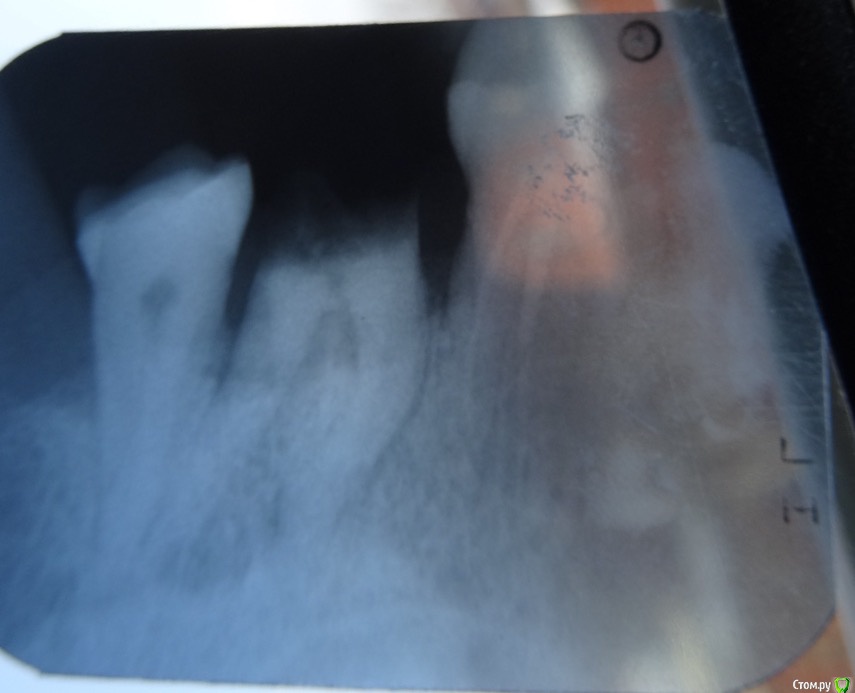

Митя23 Опубликовано 11 марта, 2020 Поделиться Опубликовано 11 марта, 2020 Добрый день!Сломался зуб 7 справа верхний.Есть ли шансы нарастить или однозначно удаление и инплант? Ссылка на комментарий

brg Опубликовано 11 марта, 2020 Поделиться Опубликовано 11 марта, 2020 удалять! 1 Ссылка на комментарий

red_butler Опубликовано 11 марта, 2020 Поделиться Опубликовано 11 марта, 2020 +1 удалять Ссылка на комментарий